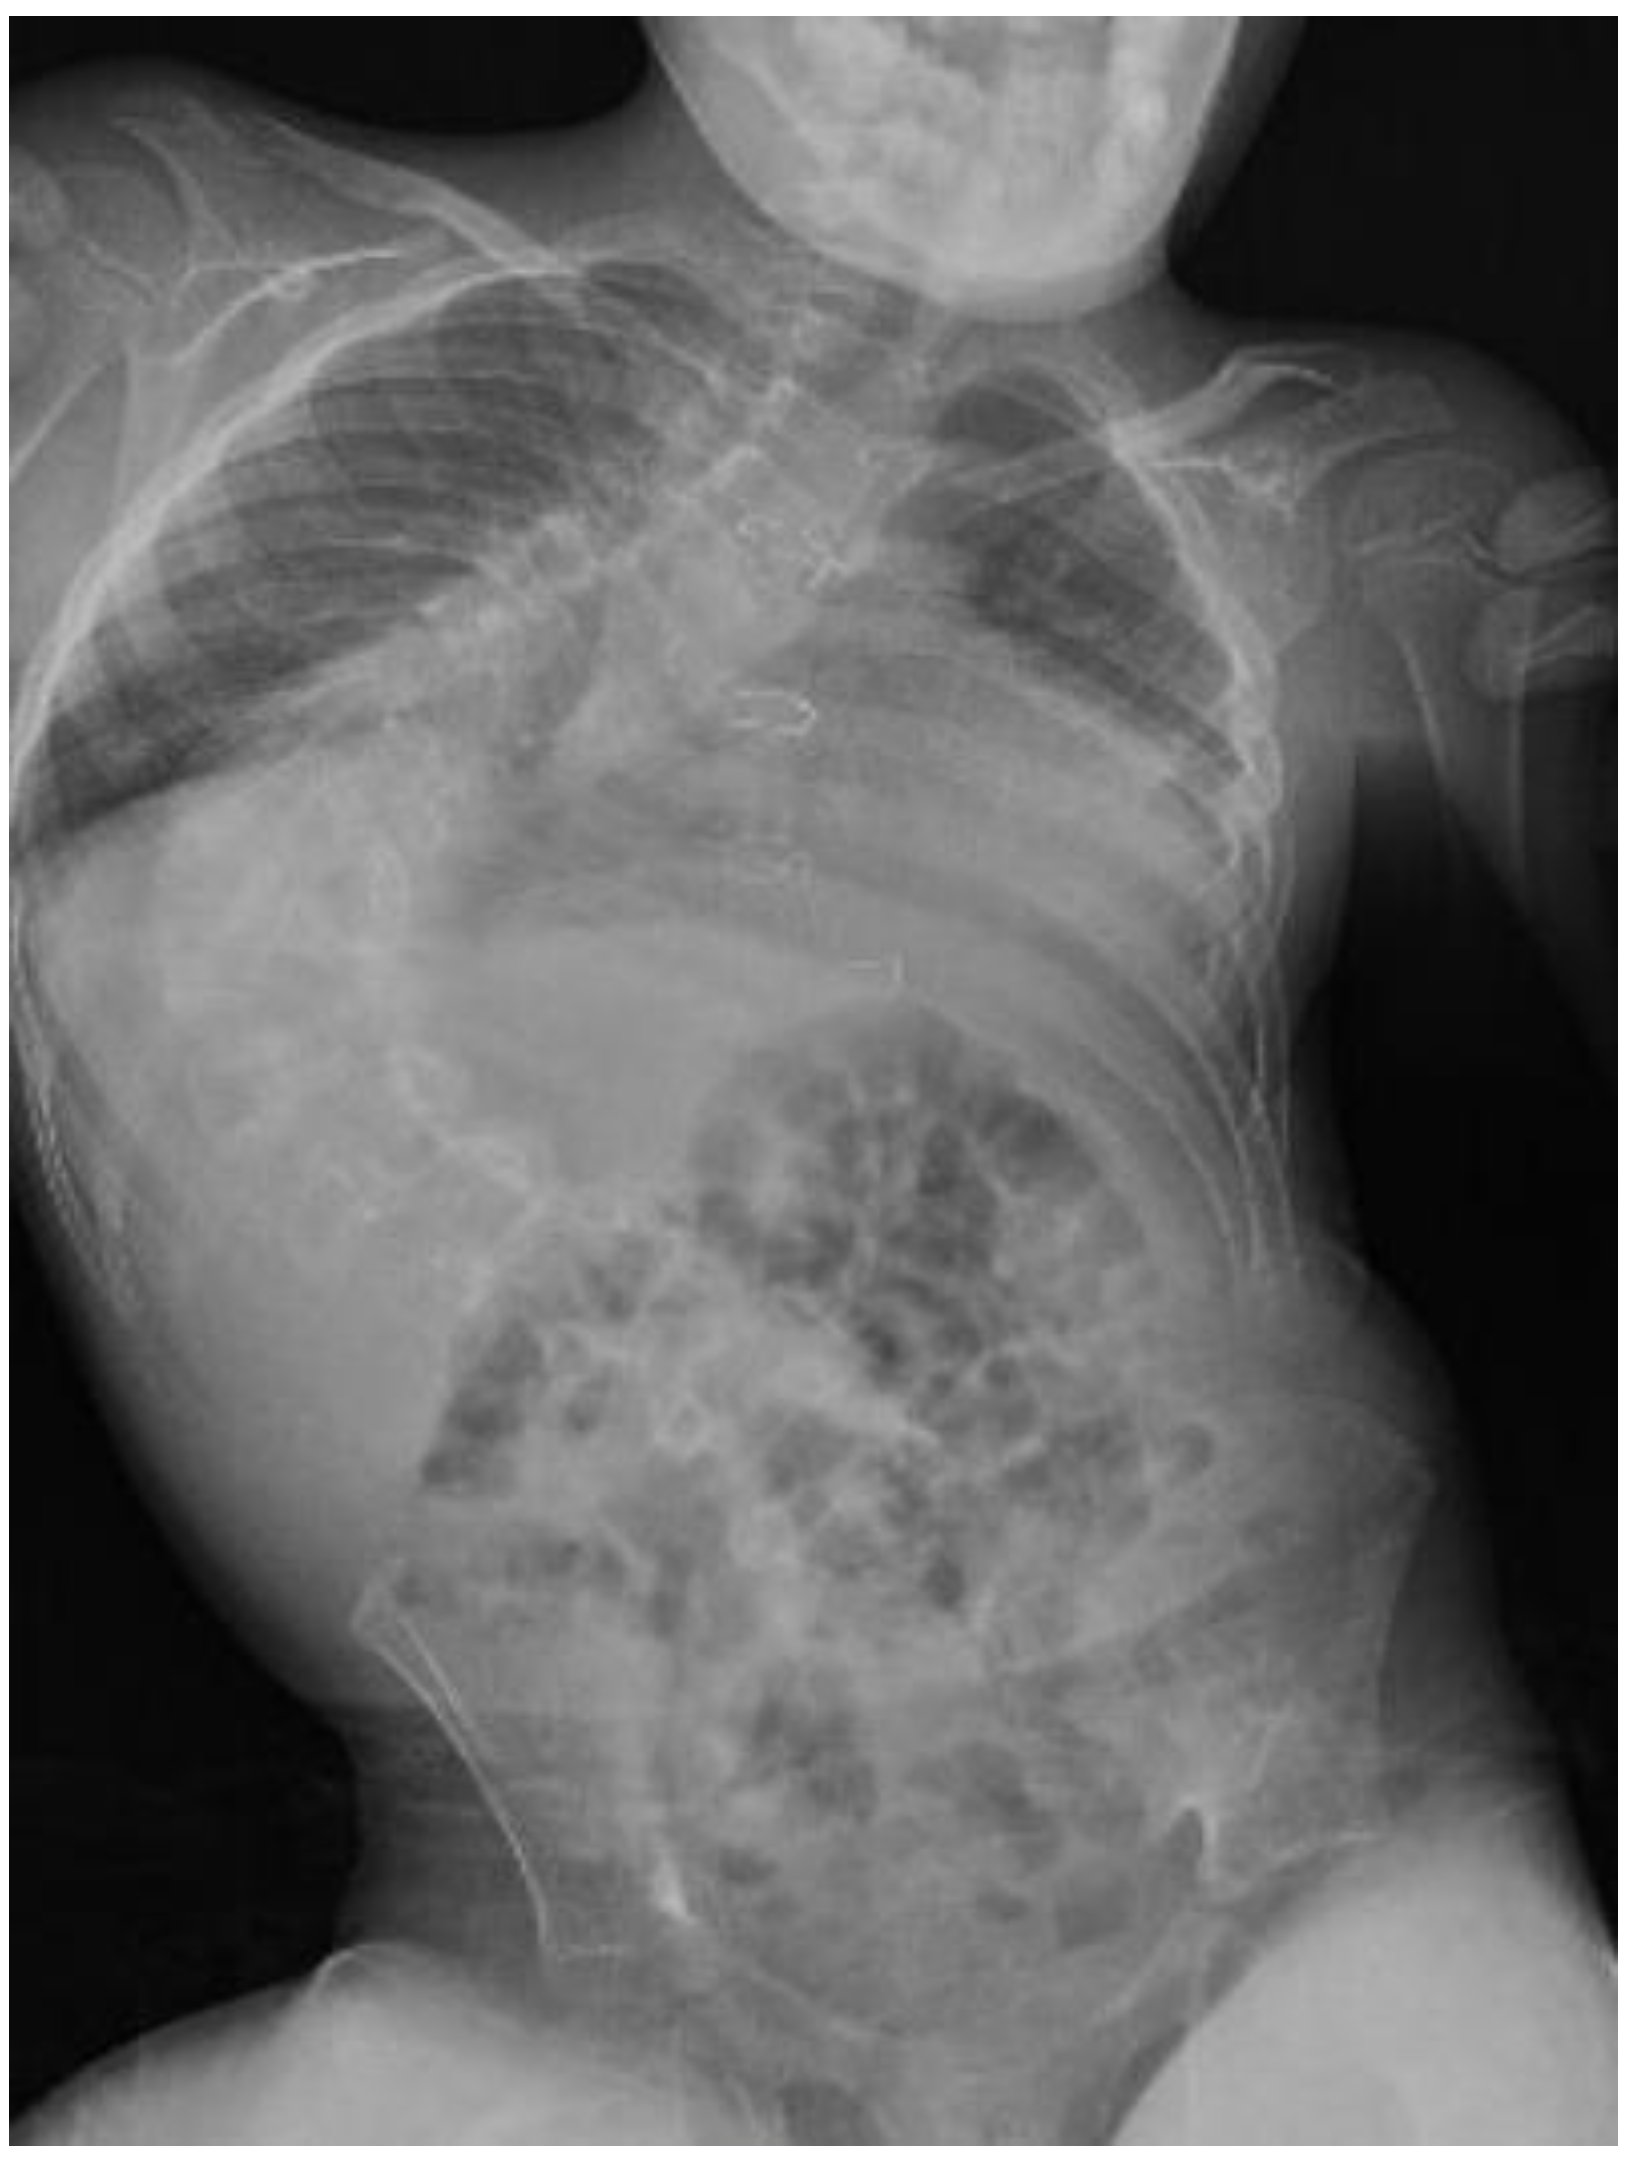

He was able to walk with support for a short distance before the surgery. His speech was limited to a few words. Facial dysmorphism was presented by a small mouth, broad nasal bridge, and strabismus. Pulmonary functions were limited by a progressive scoliosis curve. The Cobb angle was 95° (Figure 1). Spirometry was not performed because of insufficient cooperation. ECG, echocardiography (Normal systolic function with right heart dilatation, pulmonary valve regurgitation grade III, and mild stenosis of the left branch of the pulmonary artery), and other cardiovascular findings were without contraindication to the surgery. According to the endocrinologist’s recommendation, hormone substitution with hydrocortisone, levothyroxine, and somatropin was administered. The actual EEG was without epileptic activity on the chronic medication.

Figure 1. X-ray before surgery with progressive scoliosis, Cobb angle 95°.